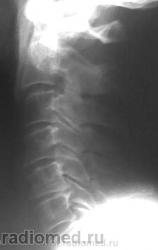

Остеохондроз, спондиллоартроз, протрузия МПД С5-С6 кзади. Что Вас смущает на этих снимках? Игра теней на уровне С6(прямой снимок)?

В теле С5 поперечное посветление в боковой, видимо и в прямой проекции.

Разглядываю эти снимки уже в 20й раз. Насколько удалось разглядеть - несращение дужки С5+артроз? меджду боковыми массами С5-6. Больше по этим снимкам разглядеть невозможно

Валентин Львович, то, что Вы пометили желтыми стрелками, изображения оснований поперечных отростков, они есть и в других позвонка. Снизу идут ножки дуг, которые накладываются на задние отделы тел и их плотные контуры делают визуально верхний угол тела более прозрачным. Это игра теней.

А что ретролистеза С5 нет?

Попробуйте провести линию по задним поверхностям тел позвонков через эти точки. Картина несколько другая. задние костные разрастания С5-С6 не должны учитываться при разметке.